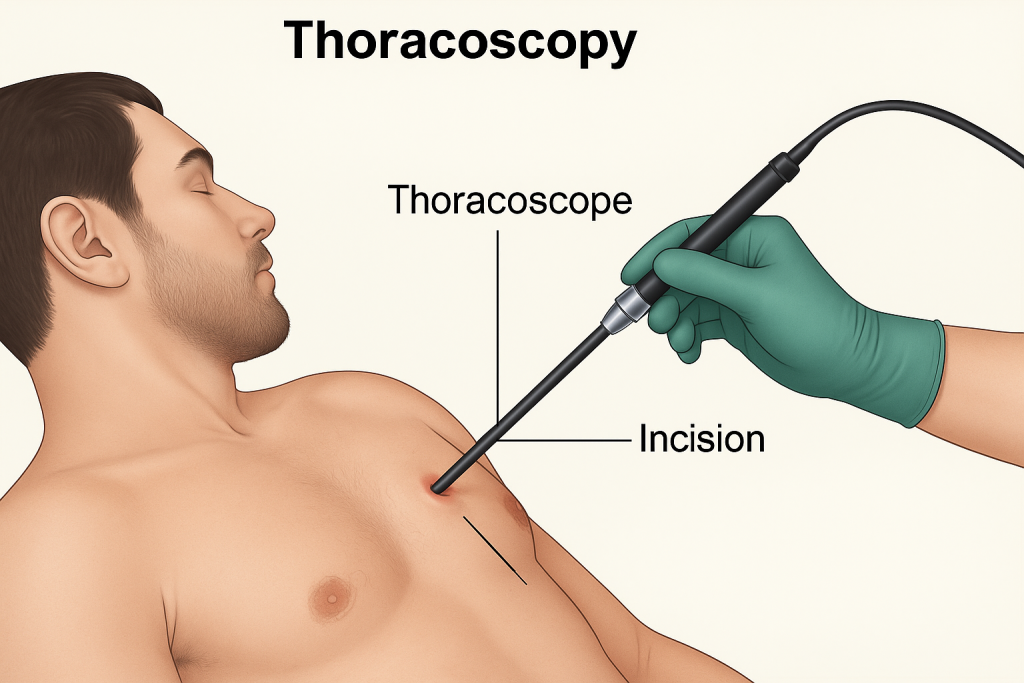

Thoracoscopy (થોરાકોસ્કોપી):

- થોરાકોસ્કોપી એ એક ડાયગ્નોસ્ટિક પ્રોસિઝર છે જેમાં એન્ડોસ્કોપની મદદથી પ્લુરલ કેવીટીને એક્ઝામીન કરવામાં આવે છે.

- આ પ્રોસિજરમાં ચેસ્ટ વોલમાં નાનામાં નાનું ઇનસિઝન મુકવામાં આવે છે અને આ ઇનસિઝન મારફતે એન્ડોસ્કોપને પ્લુરલ કેવીટીમાં ઇન્સર્ટ કરવામાં આવે છે અને તે એરિયાનું ડાયરેક્ટ એક્ઝામિનેશન કરવામાં આવે છે.

- આ સ્પેશિયલાઇઝ એન્ડોસ્કોપમાં નેરોઇંગ ટ્યુબ આવેલ હોય છે અને તેમાં આવેલ કેમેરા અને લાઇટ દ્વારા થોરાસિક એરિયાને વિઝયુલાઇઝ કરવામાં આવે છે.

- થોરાકોસ્કોપીની મદદથી પ્લુરલ ઇફ્યુઝન, પ્લુરલ ડીઝીસ અને Tumor ના સ્ટેજિંગ ને ડાયગ્નોસ કરી શકાય છે આ ઉપરાંત થોરાકોસ્કોપીની મદદથી બાયોપ્સી પણ કલેક્ટ કરવામાં આવે છે.